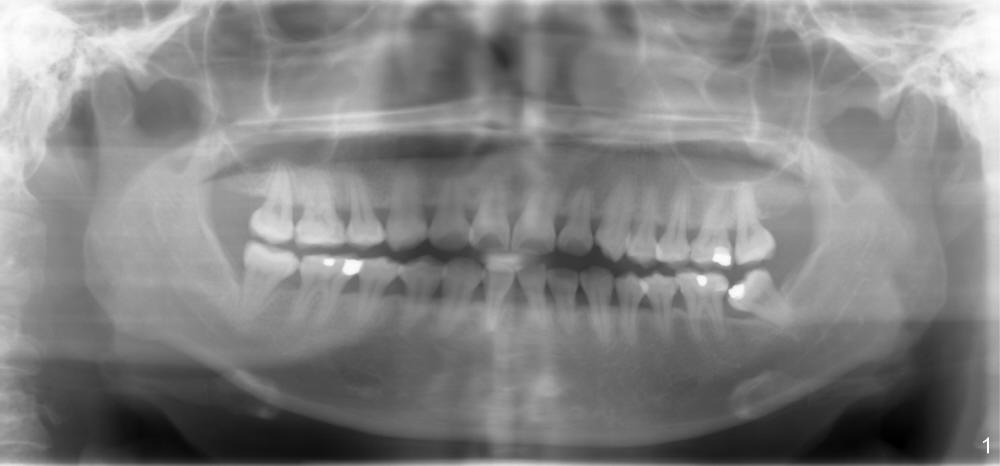

Thirty-four-year-old lady has history of ortho, but the tooth #18 tilts mesially, causing caries and food impaction between #18 and 19 (Fig.1). Chronic periodontitis is under control.